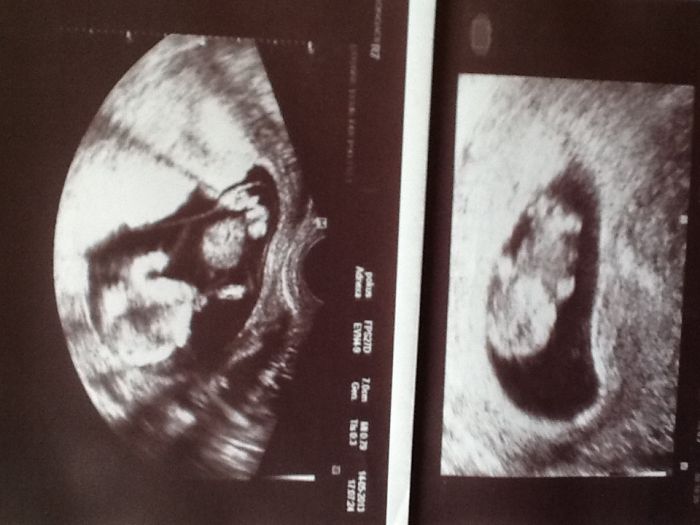

Ahojky tehulky, tak se po precteni vasi cele diskuse taky pridavam a koukam ze co doktor to jiny postup. Ja se dozvedela ze jsem tehu v 5tt a hned jsem dostala tehu prukazku, v 10tt se maly tak natocil, ze i kdyz jsem to nechtela vedet, rikala jsem si ze to bude kluk. No a 13tt to potvrdil, zase tim pindou na me uplne maval :) takze to bude chlapecek. Zitra jdu zrovna na kontrolu, podle vseho bych mela byt cca 18tt no uvidim co mi doktor povi zitra. A co se tyce testu na zadnych jsem jeste nebyla, ultrazvuk mam pravidelne co 3tydny takze fotecky se celkem sbiraji a na odber krve jdu zitra poprve, takze uplne jiny postup nez u vas. Pro nazornost jak lze poznat pohlavi uz tak brzo posilam obe fotecky :) zase je fakt ze muj doktor tu ma nej ultrazvuk a chodi k nemu na ruzna vysetreni i maminky z okoli :)

Obdivuju Tě jak na těch obrázkách něco vidíš... já ať koukám jak koukám nevidím nic..... A máte už jméno pro chlapečka???